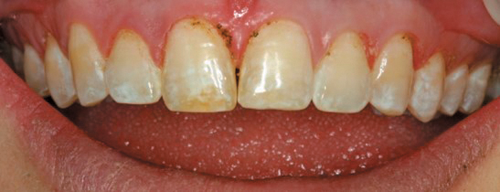

I think the use of soft tissue lasers in a smile design case demonstrates the predictability of healing in the esthetic zone, where we often have thin tissue and exact margin placement. When working on a smile design case, we want to achieve symmetry of the gingiva, and position the height of the soft tissue of the cuspids and central incisors evenly and 1-1.5 mm above that of the lateral incisors, with the gingival zenith positioned slightly distal to the midline of the teeth to help create the appearance of their mesial inclination.

To see the value of using a soft tissue diode laser, let’s look at the alternatives such as a surgical blade procedure or using an electrosurgery unit. With both these options, we need to administer an injectable local anesthetic. Using a blade, our patient will have postoperative bleeding and discomfort to manage, and we have to wait for the tissue to heal before we prepare the teeth and take a final impression. Alternatively, if we used an electrosurgery unit, we would not have the postoperative bleeding, but we would still need to wait for the tissue to heal before preparing the teeth because of tissue necrosis.

Trending article: How Genius Endo can simplify endodontics

With a soft tissue diode laser, we can often recontour the tissues after the simple application of a topical anesthetic, such as Ultracare, a 20% benzocaine gel. Using Ultradent’s Gemini soft tissue diode laser, we can select the preset power setting for “Gingivectomy” at 1.2 watts and wipe the tissue away. I have my assistant blow air on the area and hold the high volume evacuator close to remove any heat, which is the only sensation the patient might feel. Done properly, we will not see any significant changes after tissue healing.

Here is a case where the tissue has been recontoured before veneer preparation (Fig. 5), and during this same appointment the equi-gingival veneer preparations were finished and impressions were done. A few weeks later the veneers were placed and Figure 6 shows the predictability in tissue position.

Fig. 5 Fig. 6